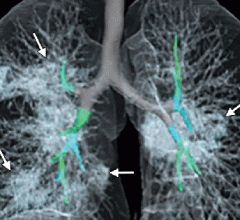

February 19, 2020 — In new research published in the journal Radiology, researchers in China cite the need for computed ...

As the 2019-nCoV Pneumonia is taking the world by storm, researchers have found a possible way to predict this virus ...